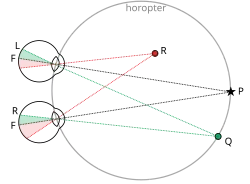

Stereopsis

The visual experience on the development of binocularity in the visual cortex. Stereoscopic vision is absent in people with amblyopia and strabismus. When IOT of the tilt aftereffect was investigated for binocularity, it was found that normal subjects have a high degree of interocular transfer, while strabismic subjects have very little.[16]